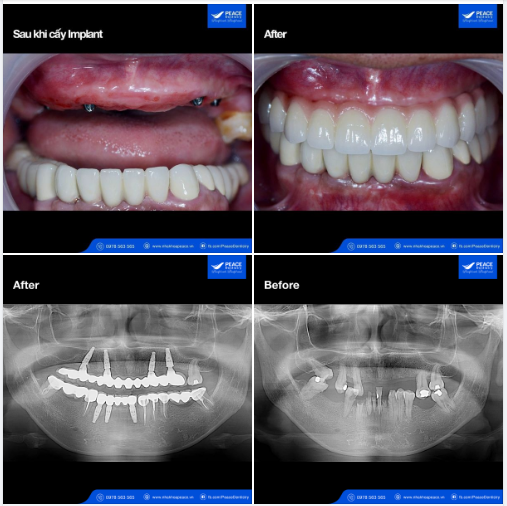

Khôi phục trọn vẹn chức năng ăn nhai và thẩm mỹ cho khách hàng lớn tuổi

Ca lâm sàng: ???-??-? ??????? (??) + ? ??????? ??̀ ??̂̀? ??̆?? ??̛́ (??) →

VẤN ĐỀ CHÍNH YẾU: Khách hàng đến Peace Dentistry với tình trạng:

✓ Hàm trên: còn 5 răng nhưng đã lung lay thấy rõ, tiêu xương, tụt nướu và để lộ phần chân răng...và tiên lượng mất răng sớm.

✓ Hàm dưới: mất 4 răng hàm nhai nhiều năm, một số răng cửa chỉ còn một phần chân răng và cũng không còn khả năng phục hình, buộc phải nhổ bỏ.

Tình trạng trên làm cho chức năng ăn nhai rất kém, đau và khó chịu khi ăn nhai và gần như chỉ ăn được các thực phẩm mềm; thẩm mỹ răng miệng kém.

CHỈ ĐỊNH ĐIỀU TRỊ CHÍNH:

✓ Hàm trên: Nhổ bỏ các răng đã lung lay (tiên lượng mất răng sớm); ??̂́? ???́? ??????? ??̛́? ???̀ với phương pháp All-on-4 Implant, phục hình tức thì.

✓ Hàm dưới: Nhổ các chân răng vùng răng cửa, cấy 3 Implant tức thì, phục hình tạm; đồng thời làm 2 cầu răng R34-37, R44-47.

KẾT QUẢ ĐIỀU TRỊ:

Với các giải pháp nói trên, khách hàng lớn tuổi đã có được cả 2 hàm răng với: chức năng ăn nhai khỏe, cảm giác ăn nhai tốt; thẩm mỹ răng miệng tôt, vệ sinh răng miệng thuận tiện. Và đặc biệt, khuôn mặt khách hàng sau khi làm răng trông trẻ hơn thấy rõ, tình trạng móm, hóp má được cải thiện một cách rõ rệt.